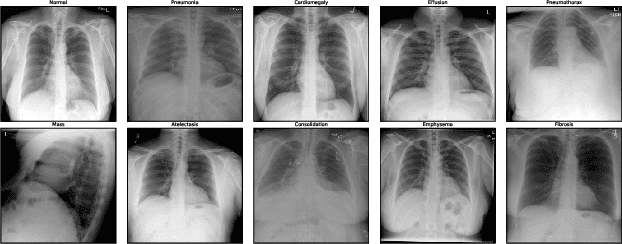

Abstract:Multimodal chest X-Ray analysis often fine-tunes large vision-language models, which is computationally costly. We study parameter-efficient training (PET) strategies, including frozen encoders, BitFit, LoRA, and adapters for multi-label classification on the Indiana University Chest X-Ray dataset (3,851 image-report pairs; 579 test samples). To mitigate data leakage, we redact pathology terms from reports used as text inputs while retaining clinical context. Under a fixed parameter budget (2.37M parameters, 2.51% of total), all PET variants achieve AUROC between 0.892 and 0.908, outperforming full fine-tuning (0.770 AUROC), which uses 94.3M trainable parameters, a 40x reduction. External validation on CheXpert (224,316 images, 58x larger) confirms scalability: all PET methods achieve >0.69 AUROC with <9% trainable parameters, with Adapter achieving best performance (0.7214 AUROC). Budget-matched comparisons reveal that vision-only models (0.653 AUROC, 1.06M parameters) outperform budget-matched multimodal models (0.641 AUROC, 1.06M parameters), indicating improvements arise primarily from parameter allocation rather than cross-modal synergy. While PET methods show degraded calibration (ECE: 0.29-0.34) compared to simpler models (ECE: 0.049), this represents a tractable limitation addressable through post-hoc calibration methods. These findings demonstrate that frozen encoder strategies provide superior discrimination at substantially reduced computational cost, though calibration correction is essential for clinical deployment.